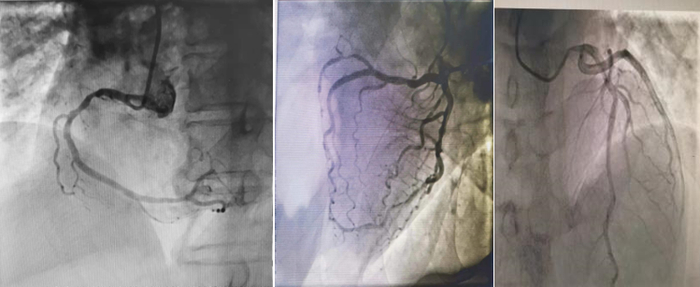

冠脉造影(2023年4月24日):LM、LAD、LCX均未见明显狭窄,RCA中远段30%狭窄。

3、辅助检查:2023年4月20日心电图提示窦性心律,大致正常心电图;2023年4月22日心脏彩超提示心脏结构及功能未见明显异常;冠脉造影提示LM、LAD、LCX均未见明显狭窄,RCA中远段30%狭窄,排除冠心病。